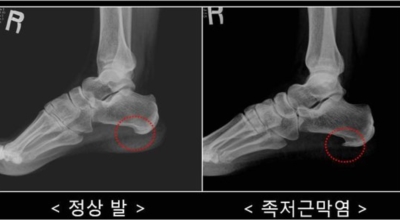

족저 근막이란 발가락 시작지점부터 발뒤꿈치뼈까지 발바닥 전체를 감싸고 있는 두꺼운 막을 말해요. 족저 근막은 발바닥 아치를 지속시켜 발바닥이 지면을 내딛음으로써 나타나는 충격을 흡수하는 중요한 역할을 수행하고 있어요. 이 족저 근막에 일차적으로 서서히 조직 손상이 일어나고 계속적인 활동으로 인해 염증이 커지면서 발 뒤꿈치 부근 통증을 유발하게 되는데 염증은 무리하고 반복적인 동작, 과도한 사용으로 마찰에 의해 발생해요.

족저근막염은 여러가지 원인으로 발생할 수 있기 때문에 정확한 원인을 파악하고 적절한 치료를 받는 것이 중요해요. 구조적으로 평평한 발을 가지거나 정상보다 높은 아치를 가진 사람들은 족저근막염이 발병할 가능성이 더 큽니다. 다리 길이의 차이나 발 형태의 해부학적 이상도 족저근막염에 걸리기 쉽습니다.

주요 증상은 통증으로 발뒤꿈치 안쪽이 아주 아프며, 맨발로 바닥을 걸을 때 걸음을 내딛을 때마다 통증이 있어요. 가장 심한 통증은 아침에 일어나 첫 걸음을 뗄 때인데, 밤에 족저근막이 수축하다가 발에 체중이 가해지면서 갑자기 늘어나는 현상입니다.